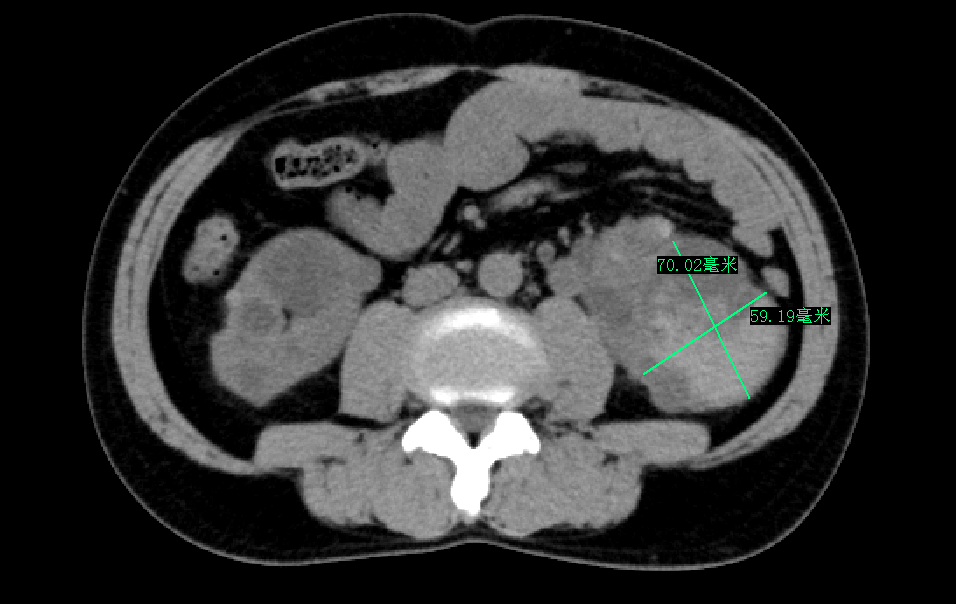

三个月前,林先生 毫无征兆出现了肉眼血尿 ,且持续多日不见好转,这才让他慌了神,急忙再次来到我院就诊。完善双肾 CT平扫提示:双侧多囊肾, 左肾较大囊肿已达7厘米。 经过对症处理病情曾好转,但入院一周前血尿再次复发,自行服药无效后,林先生决定重返医院泌尿肾病科,寻求根治。

鉴于 患者左侧肾囊肿体积较大,且存在出血和机化情况 ,若不及时治疗,不仅可能造成患侧肾脏损伤、压迫周边血管及组织,还可能导致病情进一步恶化。谢庆祥教授团队与患者及其家属充分沟通后,决定采用 创伤小、手术时间短、出血少、恢复快的腹腔镜肾囊肿去顶减压术 。